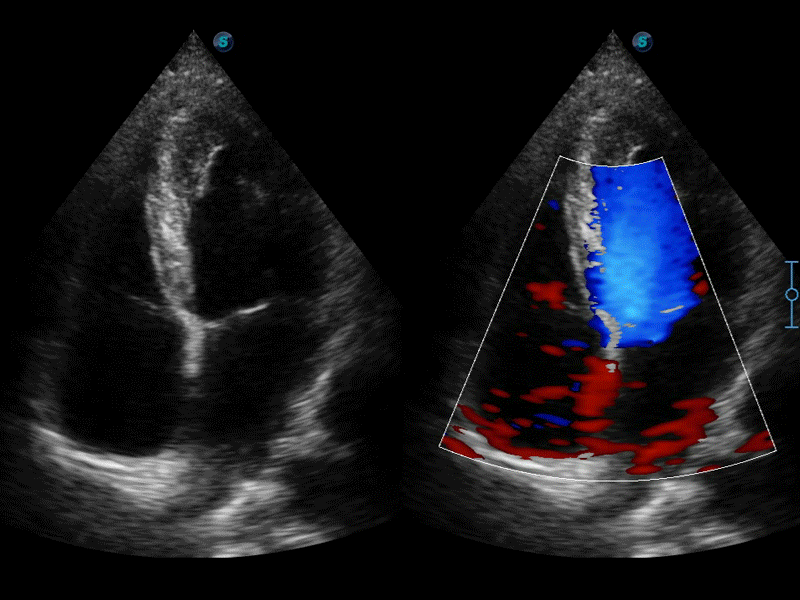

自動識別前后壁內膜厚度,為心血管疾病早期評估提供快速準確依據。

自動識別收縮和舒張末期心肌內膜,自動計算射血分數EF值。